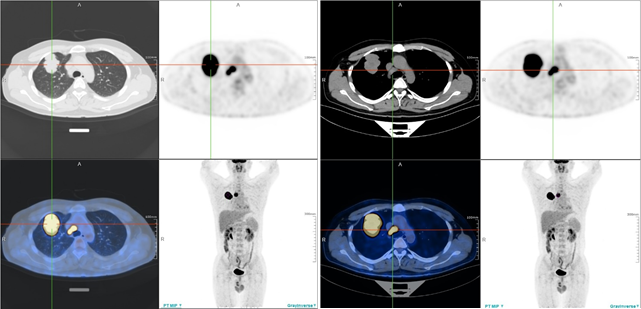

PET/CT(2020-11-24):右肺上叶前段伴糖代谢增高团块影,大小约56.7mm*51.1mm边缘呈分叶状,最大SUV值28.04;纵隔内气管右旁见糖代谢增高淋巴结,大小约16.9mm*11.8mm,最大SUV值22.01。考虑为肺腺癌伴淋巴结转移。

PET/CT提示右肺上叶前段肿块及纵隔内气管右旁有不同程度的糖代谢摄取

疗效评估(2021-2-23):两周期后,胸部CT、PET/CT提示肿物及淋巴结缩小,SUV值降低;ctDNA阴性。疗效评估提示疾病PR,靶向治疗有效,预期可完全切除。

PET/CT提示肿物及淋巴结糖代谢摄取均降低